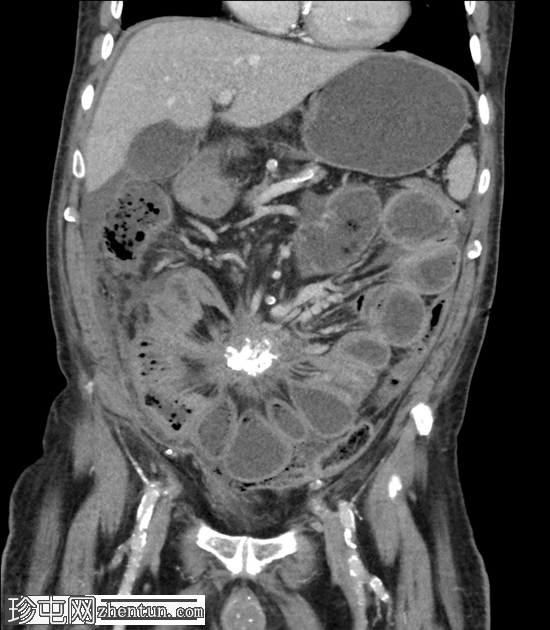

矢状位增强扫描(门静脉期)

肠系膜可见一软组织密度增高的肿块,大小为34 x 67 mm,部分钙化,边缘呈毛刺状,牵拉多个小肠袢,提示存在促纤维增生反应。

肠系膜上动脉(SMA)与该肿块关系密切。

肠系膜充血和肠壁增厚。近端小肠轻度扩张。

根据大小标准,未见腹盆腔淋巴结肿大。

右下腹可见腹膜结节,最大结节大小为28 x 19 mm。

大网膜呈结节状增厚。

少量腹水和胸腔积液。

未见其他转移。

未发现疑似小肠原发肿瘤

显著的动脉粥样硬化、多发性小肾梗死和非梗阻性结石。